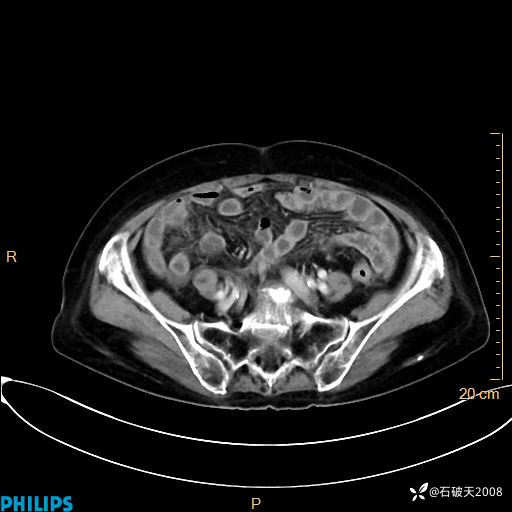

静脉期